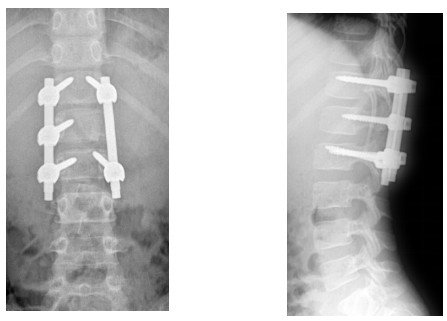

10歲小孩術(shù)前增強(qiáng)MR

術(shù)后復(fù)查不固定位置良好